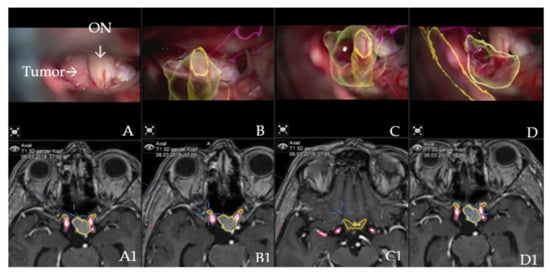

Figure 2. AR accuracy check. Patient no. 21 underwent a resection for suprasellar meningioma via right pterional approach. (A) Microscope video with focus on the tumor following exposure, with (A1) T1-weighted post-contrast MRI axial view of standard navigation display with segmented objects (tumor, optic chiasm and nerves in yellow and carotid arteries in violet). Focus of the microscope is shown as seen on the standard navigation display. (B) Microscope video with head-up display and 3-dimensional (3D) visualization of the segmented objects during the resection, with focus on right optic nerve, which shows high accuracy with the intraoperative situation. (B1) T1-weighted post-contrast MRI axial view of navigation, with focus on right optic nerve. (C) Microscope video with head-up display and 3D visualization of tumor outline, optic nerve and ipsilateral carotid artery following tumor resection with focus on the skull base with (C1) T1-weighted post-contrast MRI axial view of navigation. (D) Same as in C, microscope focus is on the contralateral carotid artery; segmented tumor outline and the course of the contralateral optic nerve are visualized with (D1) T1-weighted post-contrast MRI axial view of navigation, which shows focus of the microscope as seen on the standard navigation screen.

Augmented reality: The major indications to select a patient for surgery using the AR application were invasive tumors with encasement of the carotid and medial cerebral arteries, all tumors with close relation to the optic chiasm, giant tumors (tumor volume > 10 cm3) or recurrent tumors. Accuracy of patient registration and microscope registration were the two dependent variables for clinical AR accuracy. Microscope registration accuracy was checked by applying the AR visualization of the reference array outline. Landmark checks were successfully performed, apart from checking the target registration error (TRE), which confirmed high accuracy and excluded errors due to potential shift (Figure 2).

AR improved orientation in the surgical field for all patients as it reliably visualized the structures of interest and closely matched them to the visualized objects and the visible tumor outline. This was particularly useful in giant tumors with encasement and displacement of the cerebral arteries and compression of the optic chiasm (patients 4, 6, 8, 9, 10, 12, 13, 14, 18, 20, 22, 27, 31, 32, 33 and 36) as well as in cases of recurrent tumors (patients 24 and 35). No injuries to critical neurovascular structures occurred. The tumor was visualized in all patients, followed by vessels of interest (27 patients or 62.3%) and the optic chiasm and optic nerves in 22 patients, or 56.4%. Individual objects or HUDs could be switched off on the preference of the surgeon, in the case of AR information overflow. If this was the case, further AR support was provided by the standard navigation display and AR display on the video screens, which allowed the assisting staff to monitor the surgery, thereby serving as an educational tool.